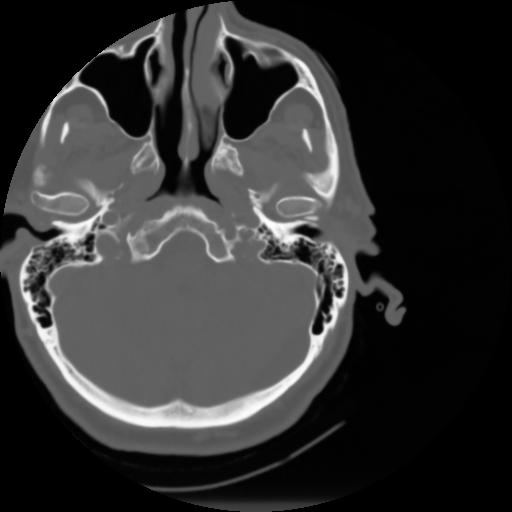

3 CEREBRO,,Axial,3.0,CEREBRO,,